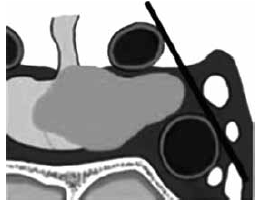

Observe a imagem.

Um macroadenoma que possui extensão lateral que termina entre a linha intercarotídea e a margem lateral do seio cavernoso é classificado como KNOSP: